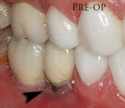

Common uses of dental implants

Mouth with many implant supported teeth where it is difficult to distinguish the real teeth from the prosthetic teeth.

Individual teeth were replaced with implants where it is difficult to distinguish the real teeth from the prosthetic teeth.

Implant retained overdenture

Movement in a lower denture can be decreased by implants with ball and socket retention.

Implant retained fixed partial denture (FPD)

A bridge of teeth can be supported by two or more implants.